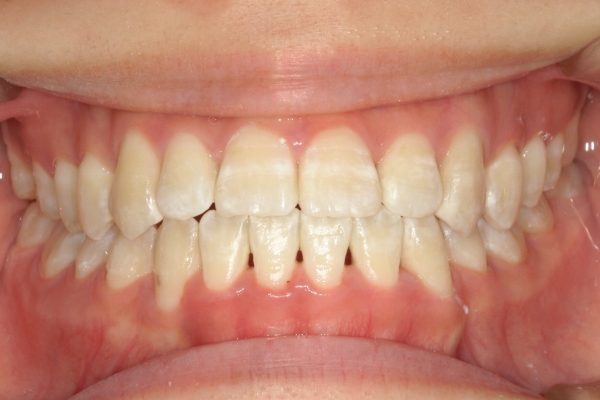

AFTER

治療後

骨格的に下あごが前下方に長いことが原因で、受け口、開咬(前歯が当たらない)の症状がでていました。また下あごが右にずれており、その影響で上下の歯列正中(真ん中)の大きなずれも生じていました。顎変形症手術も選択肢の一つでしたが、患者さまの希望もあり、下顎左側小臼歯の抜歯をして通常の歯列矯正で治療をしました。

治療後は、前歯、奥歯の噛み合わせが整い、上下の歯列の真ん中が一致しました。歯列全体のアーチも安定し、機能面・審美面のどちらも大きく改善されました。